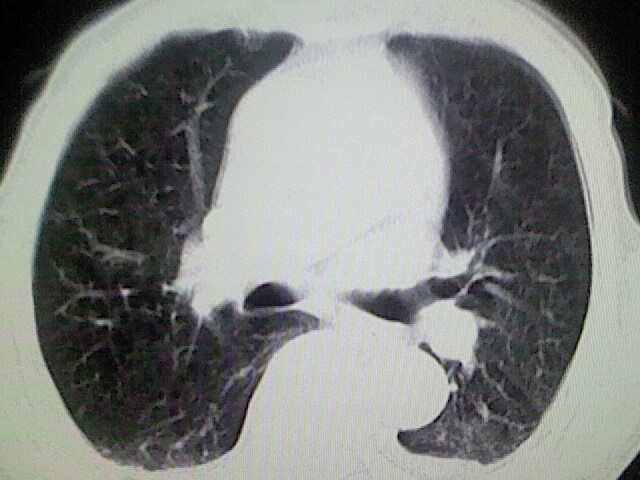

以下是引用zsl6918在2008-8-28 16:49:00的发言:[br]双肺炎性病灶,食管狭窄估计与心房增大压迫所致。

以下是引用xulianj在2008-8-28 20:36:00的发言:[br]慢支肺气肿伴感染,右上肺陈旧性结核;食道建议胃镜检查。

以下是引用wqs571018在2008-8-28 21:18:00的发言:[br]慢支继发感染,右上肺陈旧性结核;食道建议胃镜检查。